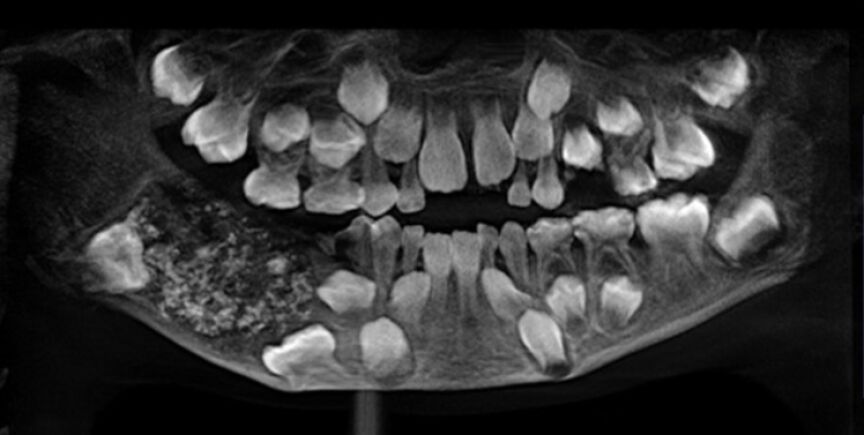

Un niño de 7 años ha sido intervenido durante cinco horas en el Hospital de la Universidad de Saveetha (India), una operación en la que le extrajeron la friolera de 526 dientes de su boca.

P. Ravindran llevaba arrastrando un fuerte dolor en su mandíbula desde los 3 años, llegando al centro médico con una importante hinchazón. Le realizaron diversas pruebas, tras las que llegaron a la conclusión de que tenía varias estructuras duras dentro de su mandíbula.

"Abrimos la mandíbula después de administrar anestesia general y vimos una bolsa dentro que pesaba alrededor de 200 gramos. Fue cuidadosamente removido y luego se encontró que contenía 526 dientes", explica P. Senthilnathan, profesor del Departamento de Cirugía Oral y Maxilofacial del Hospital.

'Odontoma compuesto' es el nombre que ha recibido esta peculiar dolencia, cuyo origen podría ser genética o ambiental, como reconocía el doctor Pratibha Ramani, profesor y jefe del Departamento de Patología Oral y Maxilofacial.